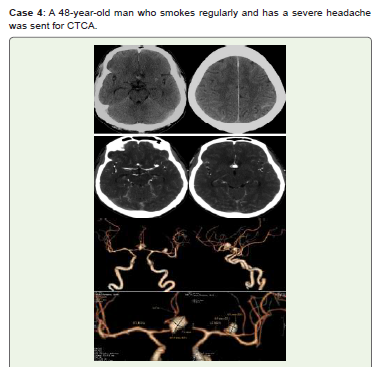

Figure 4:Acute SAH is visible at the tentorium cerebelli and cerebral sulci

interhemispheric fissure on noncontrast CT (A, B). Multilobed medium ACOM

saccular aneurysms measuring 10.8x7.6 mm and left MCA bifurcation small

saccular aneurysms measuring 6.1x4.9 mm are visible in CTCA axial (C, D)

and 3D-VR images (E–H). He received conservative care and did not return

for a follow-up.